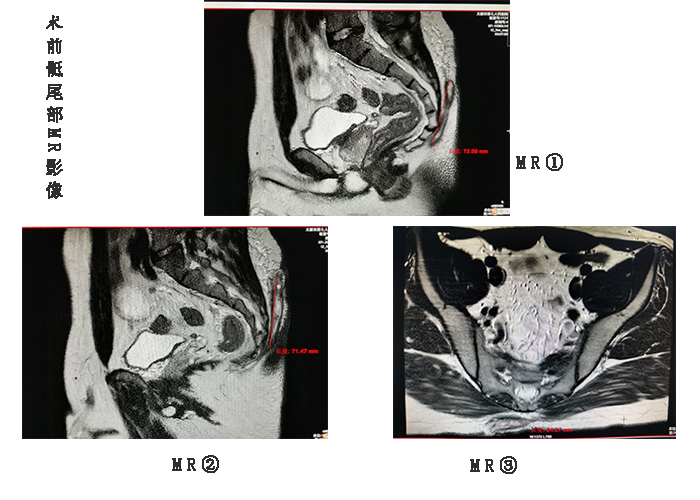

在完善一系列术前相关化验检查后,翟主任组织团队分析了患者的病情,从MRI的结果来看,病灶的范围比预想的还要严重,思忖片刻,翟主任拟定完整切除骶尾部感染灶,同时请成人快手 烧伤整形外科雷晋主任会诊,决定行骶尾部创面带蒂轴型皮瓣转移术,努力做到一期愈合。